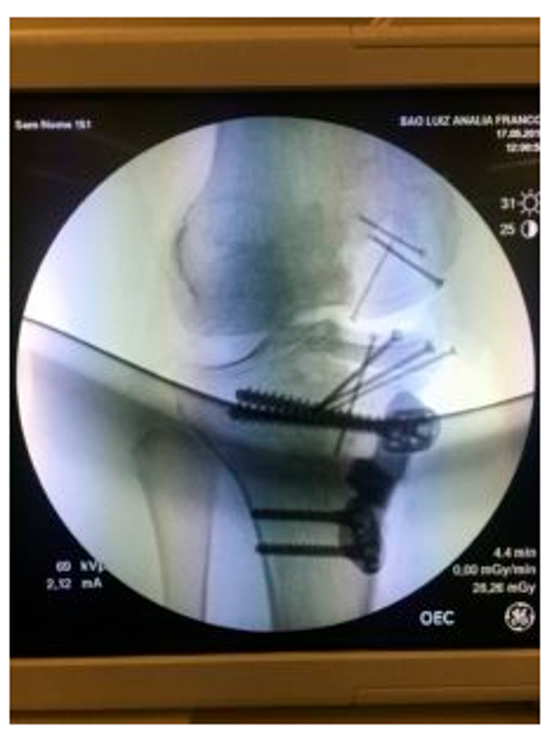

A paciente em questão é do sexo feminino, e sentia dores há mais de 6 anos. Sua lesão era uma artrose (desgaste) de toda a parte medial do joelho (côndilo femoral e tíbia medial) e também não possuía o menisco, que fora retirado em procedimento anterior.

Ela foi submetida ao transplante de osso com cartilagem com prótese biológica provinda do banco de tecidos do Hospital das Clínicas, em São Paulo. A cirurgia foi feita pelo Dr. Ari Zekcer, especialista em joelhos, e substituiu uma parte do fêmur, uma parte da tíbiacom cartilagem nova e também incluiu um transplante de menisco ao joelho.